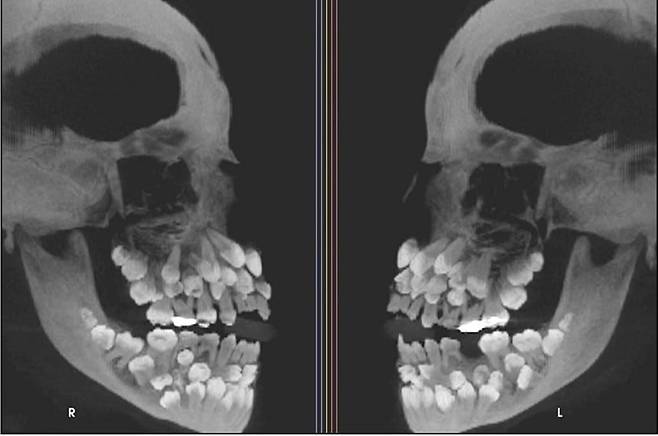

브라질 11세 소녀 입속에서 81개 치아가 발견됐다는 소식이 17일 전해졌다. 엑스레이를 찍어보니 유치 18개와 영구치 32개가 나타났다. 일반적으로 성인 영구치는 32개다. 30개 넘는 과잉치가 확인된 건 매우 드물다.

VN익스프레스 등에 따르면 브라질에 사는 11세 소녀는 위쪽 유치 1개를 뽑기 위해 병원을 찾았다. 겉으로는 큰 이상이 없었다고 한다. 엑스레이 촬영을 통해서야 ‘다발성 과잉치증’(multiple hyperdontia)이 확인된 것이다.

연구팀은 정밀 영상 검사를 통해 치아의 정확한 위치를 파악했다. 또 과잉치증이 유전 질환과 연관된 것은 아닌지 확인하는 과정도 진행했다. 이 소녀는 보통 다발성 과잉치가 동반하는 쇄골두개이형성증, 가드너 증후군, 구개열 등의 질환에 해당하지 않았다.

과잉치는 잇몸 속에 깊이 묻혀 있거나 정상 치아와 형태가 유사해 정확한 구분이 쉽지 않다. 무작정 발치할 경우 턱뼈 손상 우려도 있어 치료가 쉽지 않다. 이에 연구팀은 치과 교정과·악안면외과·치주과·보철과 등 여러 전문과와 팀을 꾸려 장기적인 치료 계획을 세우고 있다.